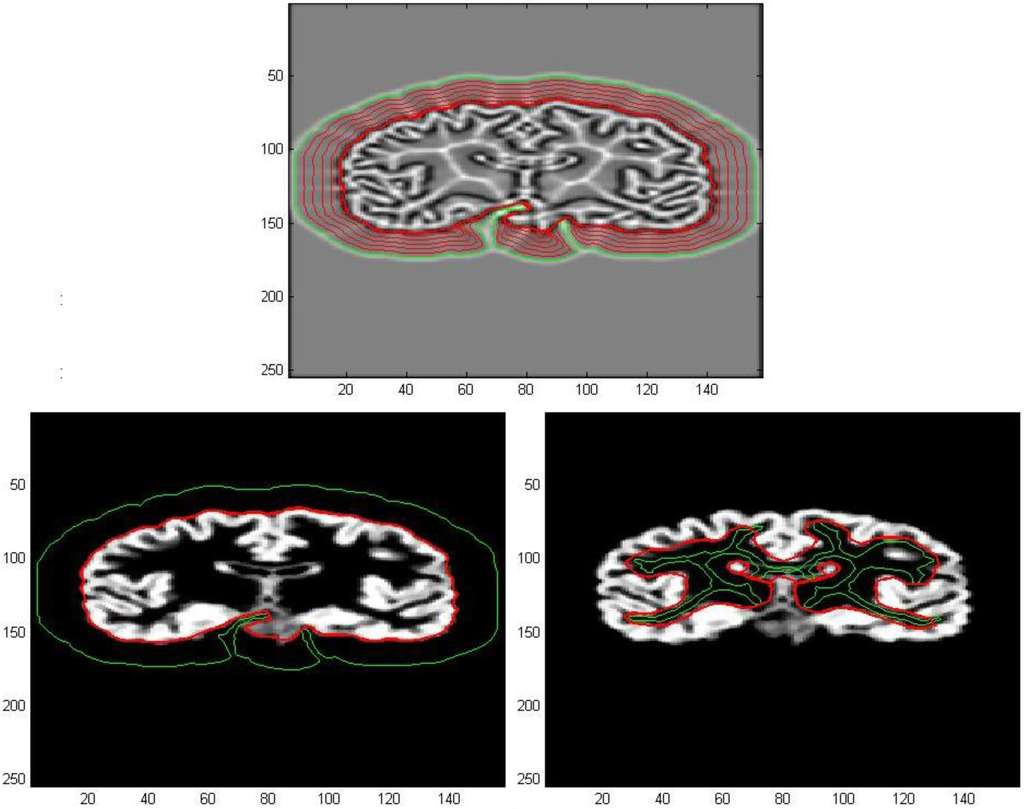

The vector field so determined, from now on called AVF field, will be used for image processing in the subsequent applications. In Figure 7a,b, we could compare the AVF field derived from Equation (8) with GGVF field obtained through Equation (7), for the same number of iterations. This model could provide us an extension of the capture range, specifically an enlargement of areas inside which any initial contour may be placed. These regions result as well defined in the divergence map because it is delimited by curves corresponding to opposite values of divergence. As a consequence, we have a complete characterization of the capture range for a vector field that will be of great help in snake initialization procedures.

Figure 7. (a) Divergence map of AVF Field; (b) Divergence map of GGVF field after 100 iterations after 100 iterations.

These areas are varying according to the number of iterations after which the flow process has been interrupted in the numerical resolution of both Equations (7) and (8). Consequently, the evaluation of the AVF vector field will be less time consuming compared to the GGVF because we could choose a reduced number of iterations in order to have a comparable capture range size and to achieve similar results. Moreover, by increasing the number of iterations, the sides of areas that delimit parts of image inside which the field is null, collapse each other, especially in conjunction with deep and narrow concavities, as can be seen in Figure 8b. Therefore, the curves of high divergence allow us to clearly identify those parts of detected edges with high curvatures that result to be the most significant from the geometrical and morphological point of view.

Figure 8. (a) Divergence map of AVF field; (b) Divergence map of AVF field after 60 iterations after 180 iterations.